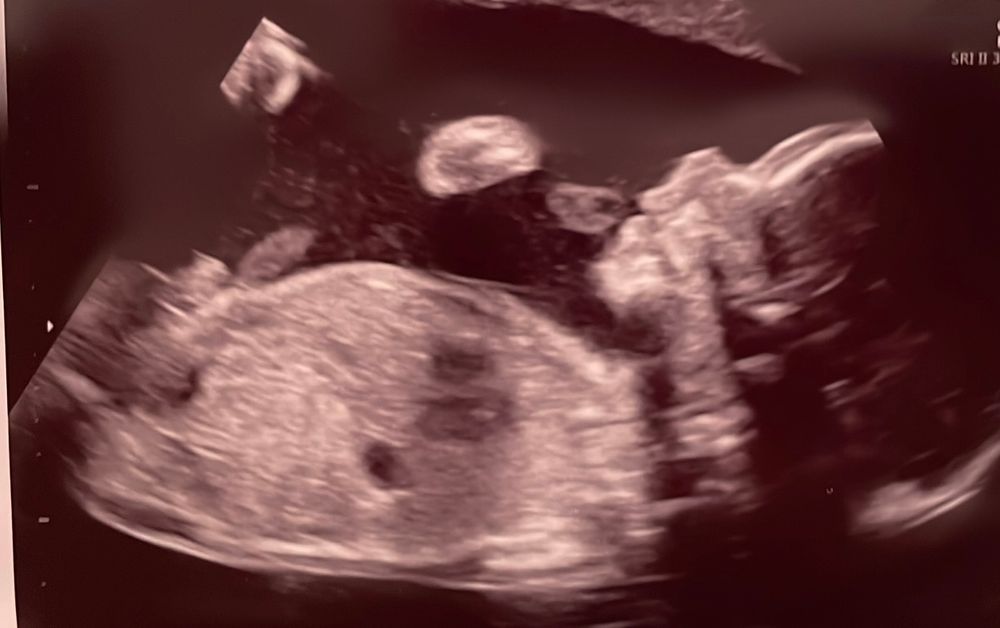

Второе узи и переживания про пол😒

Очень красивый мальчонка на снимке! Красавец! Он точно любит мамочку, оставьте и вы ложные печали - малыш должен чувствовать как его любят в ответ! Просто постарайтесь успокоиться, все идёт своим чередом)

Ой, да не расстраивайтесь! Разнообразие - это же здорово! На фотке УЗИ очень милый профиль, хороший мальчик должен получиться😉 и, в принципе, это замечательно. С мальчиком, может, и посложнее немного будет (как повезёт, конечно), но зато любви от него немерено получите😊 Я, наоборот, хотела разнополых детей 😊

Юлия Sonnце, мне когда фото показали, я прям дочку увидела(первую) ооочень похожи. И почемуто подумала что тоже дочка будет..... а тут сюрприз